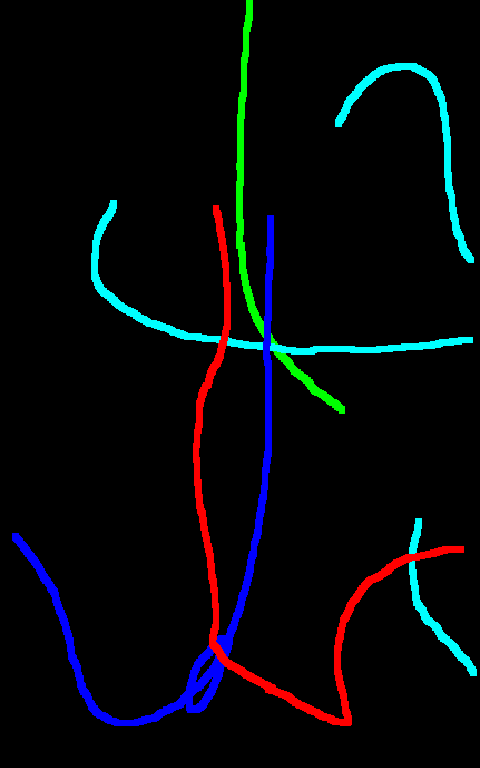

Automated catheter detection is a challenging task. Although most catheters have a radiopaque strip to facilitate detection, the strip may become less apparent depending on the projection angle. Catheters maybe confused by other similar linear structures like ECG leads and anatomy including ribs. Additionally, portions of catheters can be occluded by anatomical structures given that radiographs are a 2D projection of a 3D structure. For example, when a NGT is placed within the oesophagus, the catheter itself becomes less apparent due to the high density of the adjacent vertebrae. Finally, the number and type of catheters that could possibly appear in pediatric X-rays are unknown a priori. The catheters may be intertwined with each other thus making simple line tracing methods fail. Figure 1 gives three sample pediatric X-ray images with some common catheters highlighted in different colors.

The test dataset is collected locally and only contains frontal chest-abdominal X-rays from patients < 4 weeks old. This is the most common radiograph obtained to confirm placement of catheters such as UACs and UVCs in neonates. Currently, the test set has 35 fully labeled images with different catheter types with sample images previously shown in Figure 1. All the annotated catheters (lines excluding ECG leads) are treated as the same class in the detection.

Qualitative visual examples of the raw catheter likelihood maps obtained directly from the network without any postprocessing are shown in Figure 5. It can be seen that the proposed network at the highest scale (scale 3) achieves the best visual appearance as compared to the other methods. The maps from the proposed network at scale 2 and scale 3 look much cleaner than w/oR and fcn8s. We would attribute this to the iterative refinement of the detection results by using the recurrent module. When comparing results from the proposed network at different scales, we can see that the likelihood map from the smallest scale contains almost all line-like structures, including not only catheters but also ribs and ECG leads. This is because catheters, ribs, ECG leads look similar at a smaller scale. These irrelevant line-like structures are gradually filtered out in higher scales because catheters, especially UVCs and UACs, begin to appear as two parallel edges whereas ribs and ECG leads continue to appear as a single solid line.

There are certain situations where our proposed method would fail. Figure 7 (a) and (b) show a partially detected NGT. This mostly likely resulted from the decreased visibility of the radiopaque strip. Figure 7 (a) also shows another failure situation where the inferior portion of the UVC is occluded by the abdomen. (c) shows the case of a falsely detected unidentified line and (d) shows part of the lateral aspect of the rib cage falsely identified as a catheter.